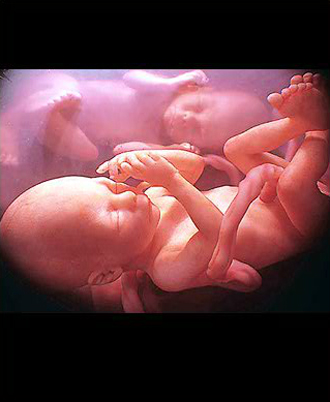

- 4차원 후기 정밀 초음파 (26~28주)

- 필수 검사

- 산전진찰 및 복부 초음파 (1회/2주)

- 막달 산모 종합 검사 (35~36주)

- 태동검사 (34~36주)